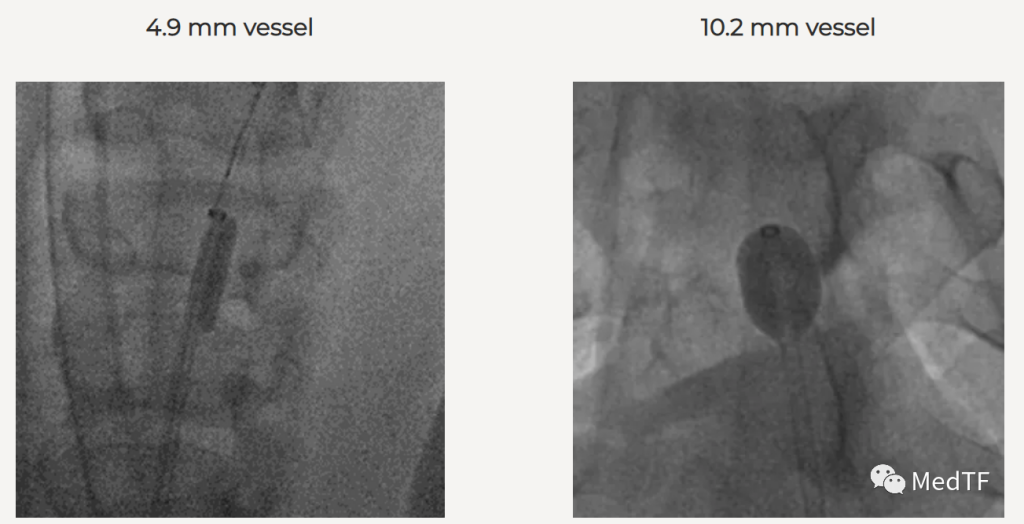

超顺应性聚氨酯球囊

Dr. Banner的超顺应性球囊能够顺应血管壁,可立即闭塞各种尺寸大小和形状的血管,最大限度地降低手术风险。